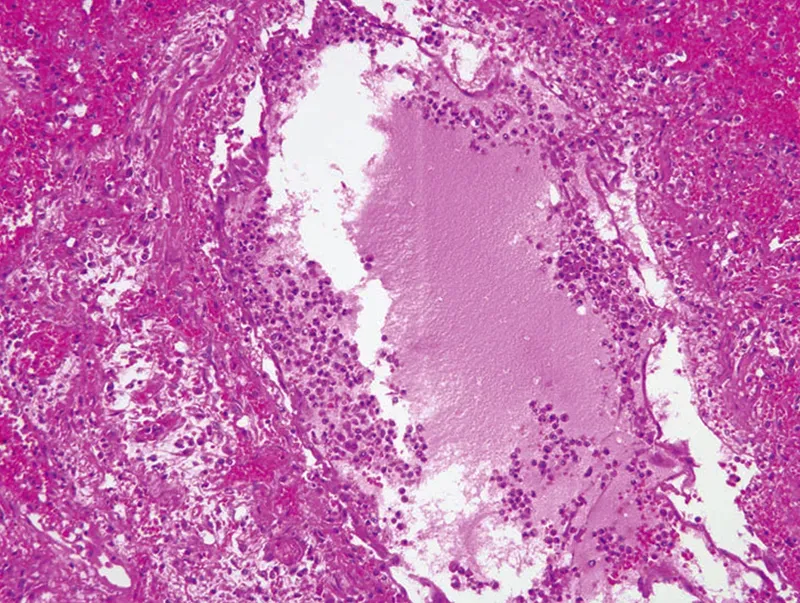

The pain, sensitivity, and fatigue from influenza's cytokines can make the host inhibit breathing and movement, so much that the concentrated and by-now toxic inflammatory soup collects in the lungs' alveoli (Image 2).

The cytokine-summoned first-responder cells are aggressive and indiscriminate in their destruction. Flooding into the tissues on the wash of leaked interstitial fluids, they use powerful enzymatic and oxidative processes to demolish both friend and foe alike (Image 3). Other cells, such as fibroblasts, simultaneously try to repair this ongoing damage, but when the cytokine-induced destruction continues, the resulting excess collagen makes tissues denser and more fibrous, further inhibiting normal perfusion and drainage.4

In musculoskeletal tissues, the plasma leakage of acute inflammation causes its characteristic swelling and redness. In lung tissue, this fluid buildup causes coughing; and if excessive or prolonged, can lead to breathing difficulties and pneumonia. What's more, capillaries damaged by the inflammatory riot can let the cytokine-rich fluids spill over into the bloodstream, resulting in systemic inflammation and multi-organ failure.5